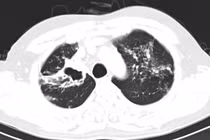

Lao phổi là bệnh truyền nhiễm nguy hiểm, có tỷ lệ tử vong cao. Việt Nam là nước có gánh nặng bệnh lao cao nhất trên thế giới. Bệnh có thể điều trị khỏi hoàn toàn, không để lại di chứng nếu được phát hiện và điều trị kịp thời.